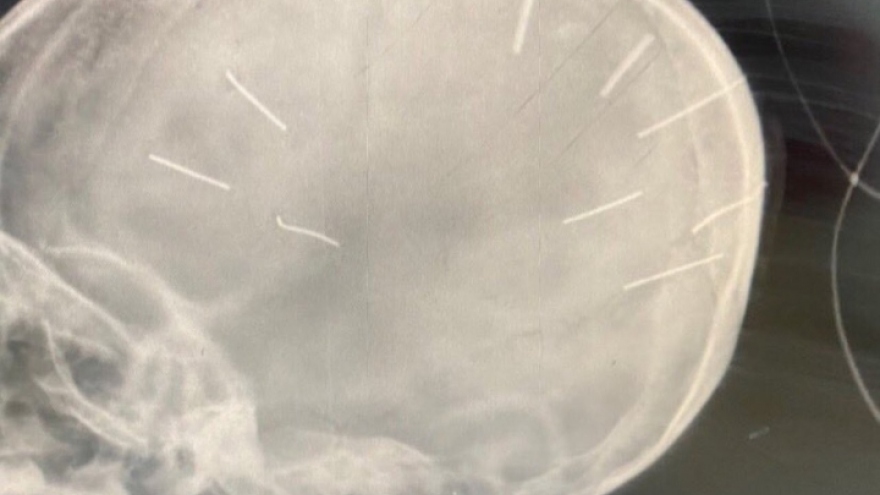

Khởi tố, bắt giam nghi phạm găm nhiều đinh vào đầu bé gái 3 tuổi ở Hà Nội tội Giết người

VOV.VN - Công an thành phố Hà Nội vừa có quyết định khởi tố, bắt giam đối với Nguyễn Trung Huyên (SN 1992, trú tại xã Thạch Hòa, huyện Thạch Thất, Hà Nội) để điều tra về hành vi giết người.